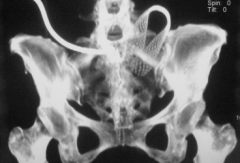

卵巢癌患者,结肠梗阻,经皮肠造瘘减压后,经造瘘口植入结肠支撑架,1个月后随访支撑架未开放 支架的两端不应该被结肠袋所覆盖。如果有这种情况发生,那么在支架未完全释放时立即调整支架的位置。有些学者建议低渣饮食以及服用矿物油,以此预防因为粪质变硬而引起支架闭塞。操作完成后,应该监测患者的生命体征和电解质,直至这些数值达到正常范围。支架安放后24小时,应行腹平片检查,再一次来评估支架的位置,检查支架有无移位或有无穿孔,以及在影像学上对比操作前后梗阻的变化。也有作者报告急诊支撑架植入后使用CT虚拟结肠镜(CT Colonography)[1]在患者的支撑架植入后的恢复期,同时对肿瘤进行分期,从而决定再行手术切除的风险和价值。常规腹部CT或超声来进行肿瘤分期,理想的方法是通过PET-CT或全身弥散加权成像技术。如果患者恢复良好,术前评估基本可以在门诊进行。 不能手术切除或广泛转移的患者,支架安植入术作为姑息治疗的手段。患者应规律随访。若出现梗阻的症状或腹膜的症状,应行影像学检查。在给患者做查体(如直肠指诊)的时候,以及给需要再次手术治疗的患者做手术的时候,需要高度重视金属支架在场内的存在,以免伤到检查或实施手术的医生。 结肠支架的植入可以在内镜引导下,透视引导下,或在联合使用两者的情况下完成。两种方法都各有优缺点。在近端结肠释放支架时,联合使用两种方法获益最大。透视下引导操作适用于降结肠远端,乙状结肠和直肠的病变。如果操作技能熟练的话,两种方法的有效率和成功率是相似的。在进行透视及内镜引导操作时,患者及操作者所接受的放射性暴露是一个非常重要的问题。有人曾在12例病人手术过程中测量过手术及透视操作的时间及总的放射剂量(dGy/cm2)。平均手术时间为57.3分钟,透视时间为20.9分钟,平均总剂量为3595 dGy/cm2。有报道称用内窥镜辅助的联合方式经肛金属支架放置术可以缩短透视的操作时间。Binker等人认为,内镜辅助下的操作可降低放射剂量,但是提高了成本,并且在所有的患者在术中需要加大镇静的剂量。 | ||||||||||||||||||||||||||||||||||||||||||||||||||||||||||||||||||||||||||||||